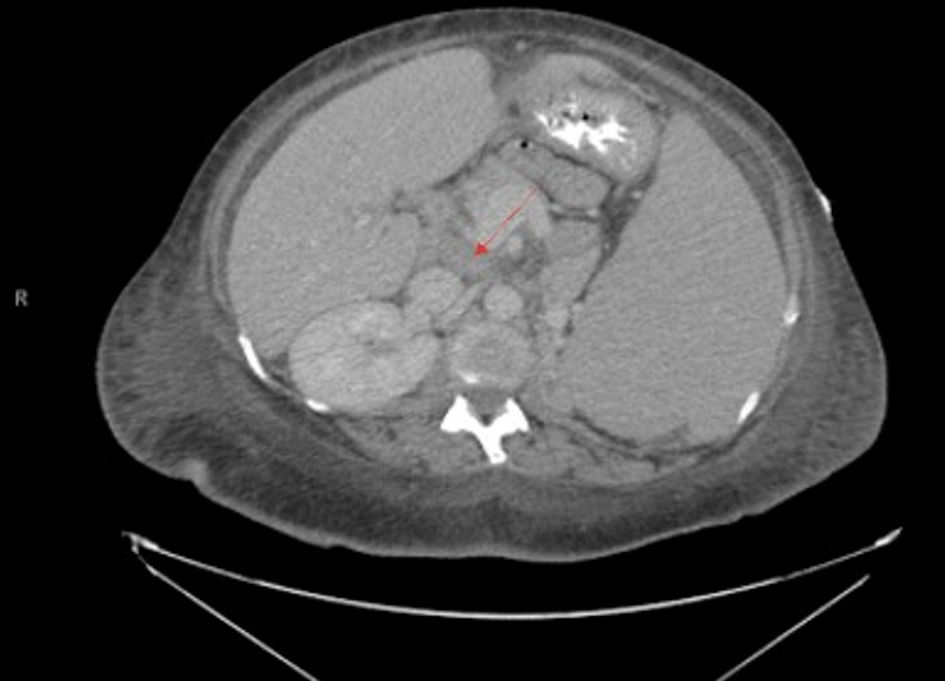

Complete blood count (CBC) showed a white blood cell count of 584 × 109/L with absolute lymphocytes of 513 × 109/L, hemoglobin at 2.7 g/dL, mean corpuscular volume (MCV) of 108.7 fL, and platelets at 60 × 109/L. The patient had no previous baseline laboratory studies available for comparison. Iron studies, ferritin, haptoglobin, vitamin B12, and folate were within normal limits. Basic metabolic profile and liver function tests were normal. A peripheral smear was obtained at outside hospital prior to transfer to our hospital, which showed some immature/atypical lymphoid cells, not thought to be blasts, and no presence of Auer rods. Viral studies including HTLV 1/2 antibody, hepatitis, Epstein-Barr virus (EBV), and cytomegalovirus (CMV) were negative. CT scan of the abdomen and pelvis revealed diffuse lymphadenopathy, splenomegaly, and lobulated uterus with partially calcified and heterogenous appearing fibroids (Figs. 1 and 2). The presence of fibroids was confirmed with transabdominal ultrasound, which showed enlarged uterus with multiple masses again most fitting with fibroids. Her uterine contour was irregular, and her myometrium was noted to be heterogenous in texture.

Figure 1. Coronal view of CT chest/abdomen/pelvis showing significant splenomegaly, measuring 23.5 cm in craniocaudal dimension. Enlarged, lobulated uterus with partially calcified and heterogenous fibroids are also seen. CT: computed tomography.